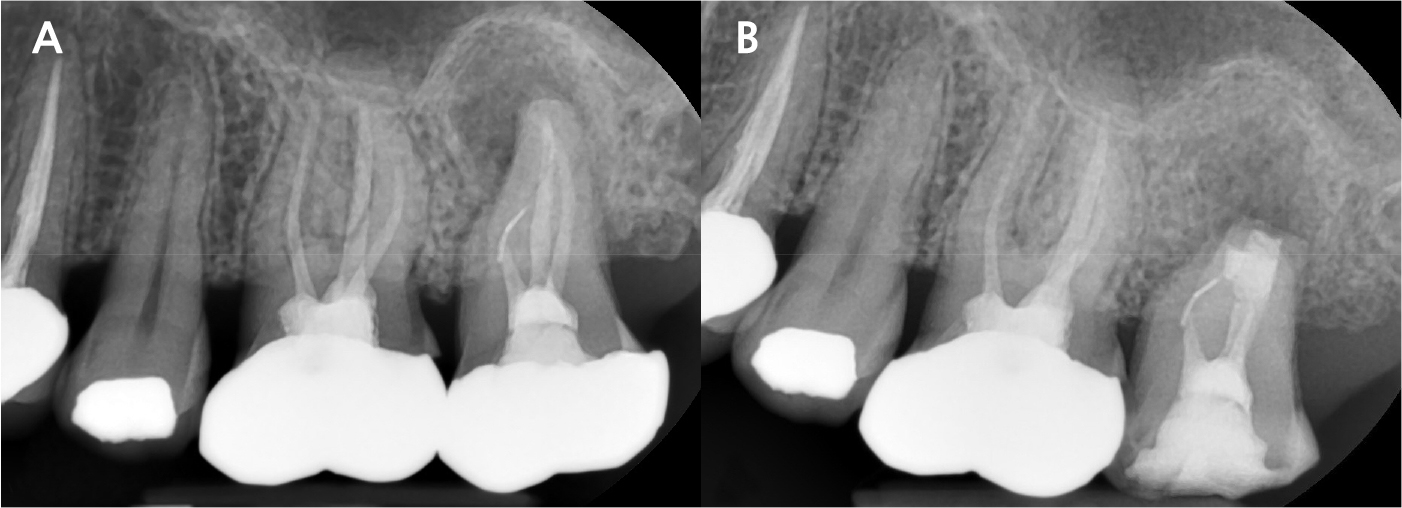

A 43-year-old female needing implant treatment and extraction of the upper left molar visited the clinic. Her upper left second molar showed second degree of tooth mobility and had a treated history of intentional replantation (Table 1). The apical lesion of this tooth disappeared after the intentional replantation (Fig. 1A, 1B). There are no signs of additional infection or periodontitis-related inflammation (Fig. 2). The alveolar bone height of this site was more than 5 mm, which facilitates the treatment plan to conduct the immediate implant placement with elevation of the maxillary sinus membrane using hydraulic pressure.

Under local anesthesia with 2% lidocaine (1:100,000 epinephrine; Huons, Seongnam, Korea), the upper left second molar was extracted with minimal damage to the alveolar bone and treated with subgingival curettage to remove apical lesions on periapical radiographs (Fig. 3A, 3B). Consequently, the maxillary sinus membrane was elevated using the hydraulic sinus lift technique through the extraction socket. Before elevation, using the sinus lift kit (CRESTAL APPROACH Sinus KIT; Shinheung, Seoul, Korea), no signs of perforation on the maxillary sinus membrane were verified.